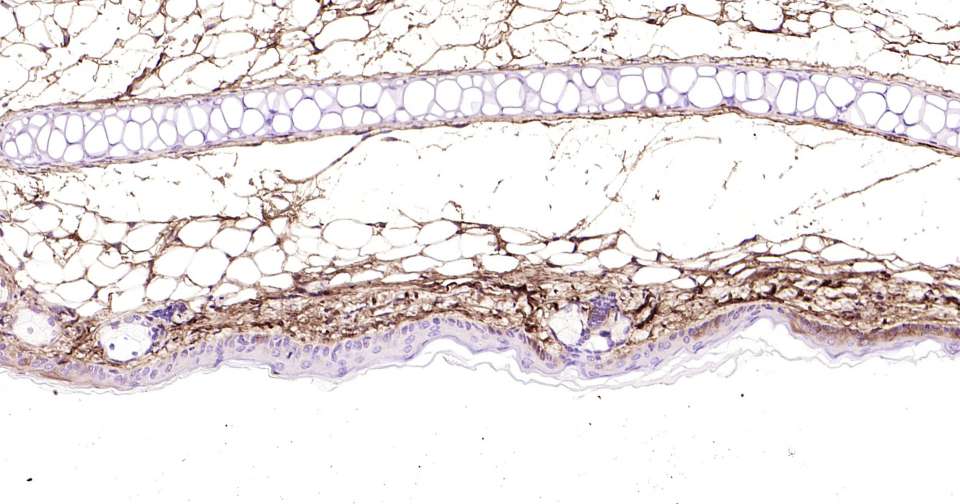

Immunohistochemical analysis of paraffin embedded mouse skin tissue slide using IHC0401M (Mouse Lumican IHC Kit).